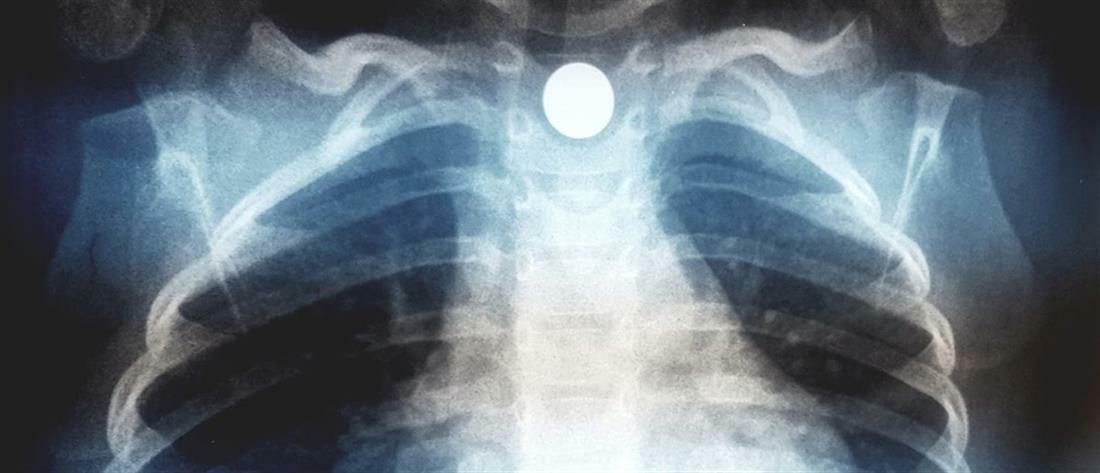

Όπως ανέφερε: «Διδακτικό περιστατικό του ιατρείου μας Κατάποση ξένου σώματος (μαγνητάκι ψυγείου) από παιδάκι 2,5 ετών και ενσφήνωση του στον οισοφάγο. Στην ακτινογραφία το αντικείμενο απεικονίζεται ευκρινώς να παρεκτοπίζει και την τραχεία του παιδιού περαιτέρω προς τα δεξιά. Το μαγνητάκι είχε πέσει στο πάτωμα και το παιδί το "ανακάλυψε" και το κατάπιε ερήμην των γονέων.

Η ενσφήνωση όλως ευνοϊκώς βοήθησε στην άμεση εκδήλωση συμπτωματολογίας από το ανώτερο πεπτικό και το αναπνευστικό.

Το αντικείμενο αφαιρέθηκε ενδοσκοπικά και το παιδί βεβαίως είναι απολύτως καλά.